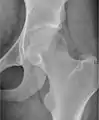

- مفصل هیپ (Hip):[14] AP و جانبی

- طرح برادران انشتاین یک نوع از بررسی مفصل ران با تأکید بر رابطه استخوان ران با حفره حقه ای است. زانو پای تحت تأثیر خم میشود و بخش میان زانو تقریباً به یک زاویه راست کشیده میشوند. به این پوزیشن، پوزیشن پای قورباغه گفته میشود.

AP لگن طبیعی

برنامههای کاربردی شامل اشعه ایکس دیسپلازی (dysplasia) استخوان هیپ میباشد.